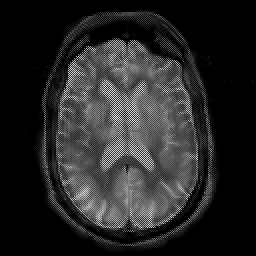

Subacute Stroke overlay -- Slice #13

[Home][Help][Clinical] Slice 13